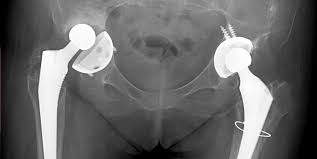

Artroplastia De Sold Centrokinetic

Artroplastia De Sold Centrokinetic Source from : https://centrokinetic.ro/fiziokinetoterapia-explicata/tehnici-chirurgicale/sold/artroplastie-sold/

Artroplastia soldului prin resurfatare tip birmingham. In ce consta artroplastia de genunchi, respectiv cea de sold? Chirurgii ortopezi din spitalul de urgenţă sfântul ioan cel nou din suceava au efectuat cu succes prima operaţie de protezare a genunchiului, deschizând astfel drumul către cea mai dificilă intervenţie din ortopedie care poate fi realizată de acum pe plan local. Cu cât proteza respectă caracteristicile articulatiei genunchiului pacientului. Cand trebuie efectuata prima revizie a unei proteze?